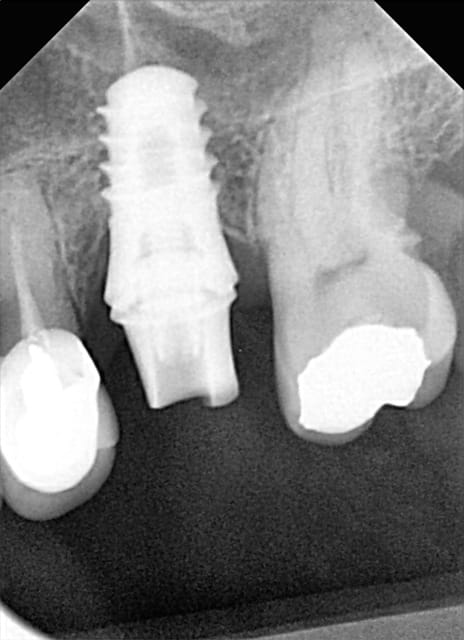

Pour Cyanolit des photos de swish plus pose en 2014

MEG1 MEG2 CH1 CH2et swiw + ric en 2015 (swish d'implant direct

j'aime le col lisse=barrière anti-bacterienne)

2 radios de 2 zimmer SPAT1 en 2010 pose et provisoire

et SPAT2 2015 comportement actuel